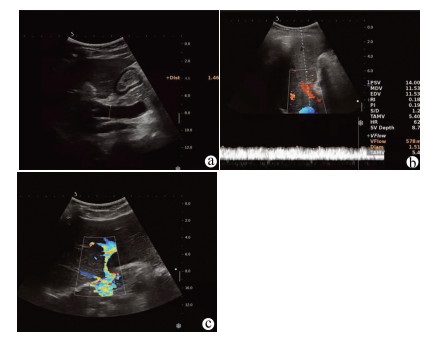

A case of idiopathic portal hypertension in chronic hepatitis B

CAI MX, LIN LW, XUE ES, et al. Color Doppler in the diagnosis of idiopathic portal hypertension and its clinical value[J]. J Clin Hepatol, 2009, 25(5): 374-376. http://lcgdbzz.org/article/id/LCGD200905023

蔡敏娴, 林礼务, 薛恩生, 等. 特发性门静脉高压症的彩色多普勒超声诊断与临床价值[J]. 临床肝胆病杂志, 2009, 25(5): 374-376. http://lcgdbzz.org/article/id/LCGD200905023